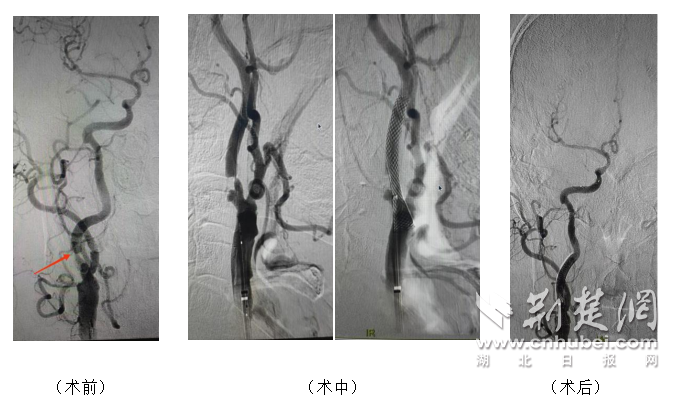

图为武汉市第五医院专家团队微创术下血管造影图。

手术当日,神经内科张细六主任介入团队在局部麻醉下,经腹股沟区微小穿刺点,在数字减影血管造影(DSA)引导下,将导丝导管精准送达狭窄部位。团队依次完成脑保护装置放置、预扩球囊扩张、支架精准释放、后扩球囊优化贴壁等关键步骤,每一步操作误差控制在毫米级。术中造影显示,狭窄血管成功扩张,脑部血流恢复通畅,患者全程清醒无不适。